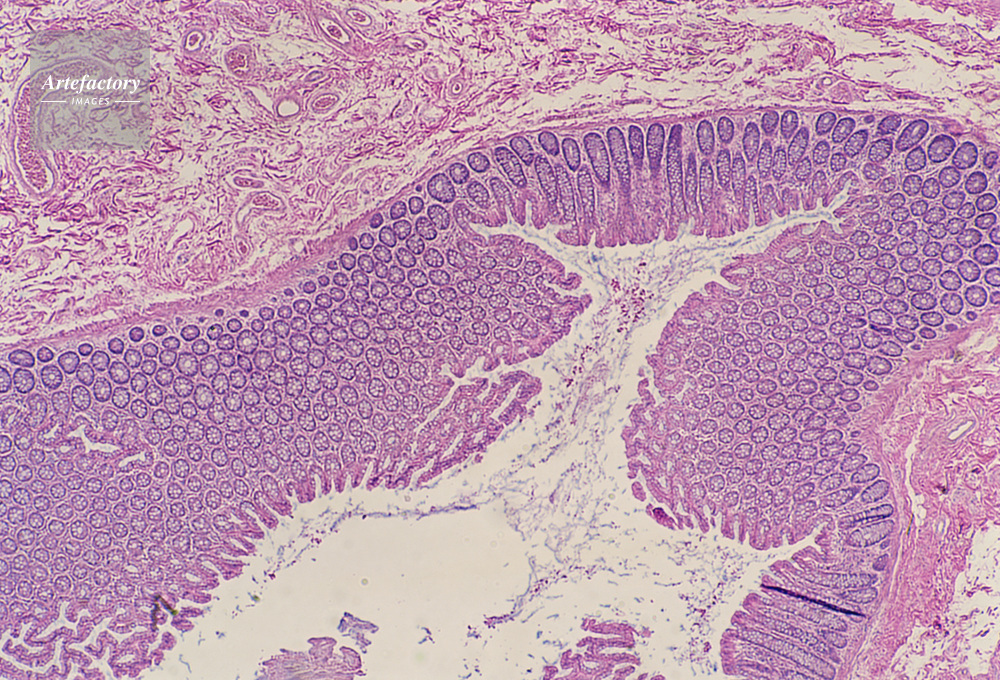

| キャプション | 結腸,人間,20倍 | 制限事項 | ||

| ソース | ピクセル数 | 5554px × 3774px | ||